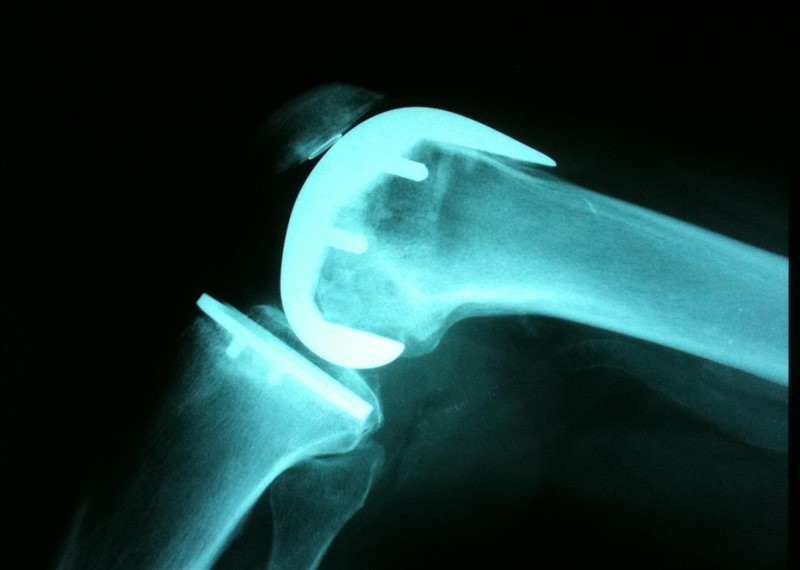

Evolución y complicaciones del reemplazo protésico del hombro

21 febrero 2019

Los eventos adversos y la necesidad de cirugía de revisión son más frecuentes de lo que se consideraba anteriormente, y para algunos casos podrían superar cualquier beneficio potencial. BMJ, 20 de febrero de 2019